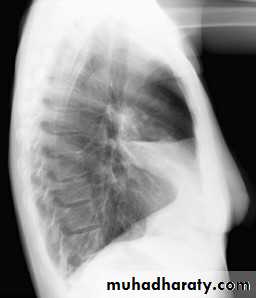

32.RT ML consolidation ( PA & lat. view )

33.RT ML consolidation (Lat. view )